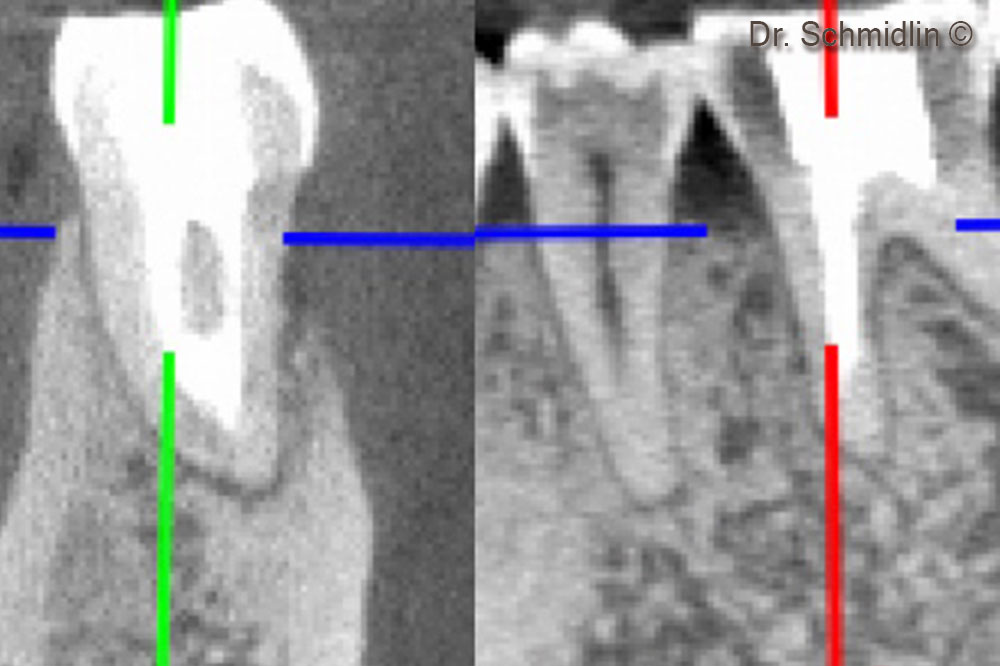

CBCT of the furcation area after 6 months

CBCT of the mesial root after 6 months